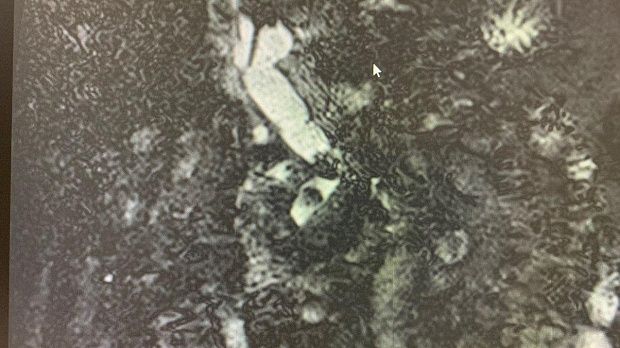

Рентгенологическая картина расширенния желчных протоков и наличие конкрментов в холедохе. Произведена эндоскопическая ограниченная папиллосфинктеротомия, отмечалось поступление темной желчи. Ревизия корзиной Дормия дали основания полагать ,что конкременты плотной консистенции.

Учитывая состояние пациента, большой степени вероятности осложнений и наличие крупных конкрементов в холедохе , принято решение следовать общепринятой тактике лечения при юкстапапиллярном расположении БДС - воздержаться от одноэтапного проведения операции с литэкстракцией. Произведено стентирование холедоха пластиковым стентом типа Pig-tail 10 Fr-130 мм, чем достигнуто адекватное дренирование желчных путей. Послеоперационный период протекал без осложнений. Биохимический анализ крови: билирубин общий-17.0 , билирубин прямой -13.0 , билирубин непрямой - 4, с-реактивный белок -24.3, скорость клубочковой фильтрации-37,4. По представленным результатам обследования в послеоперационом периоде, можно отметить положительную динамику в показателях пигментного обмена. Пациент в удовлетворительном состоянии выписан на амбулаторное лечение .